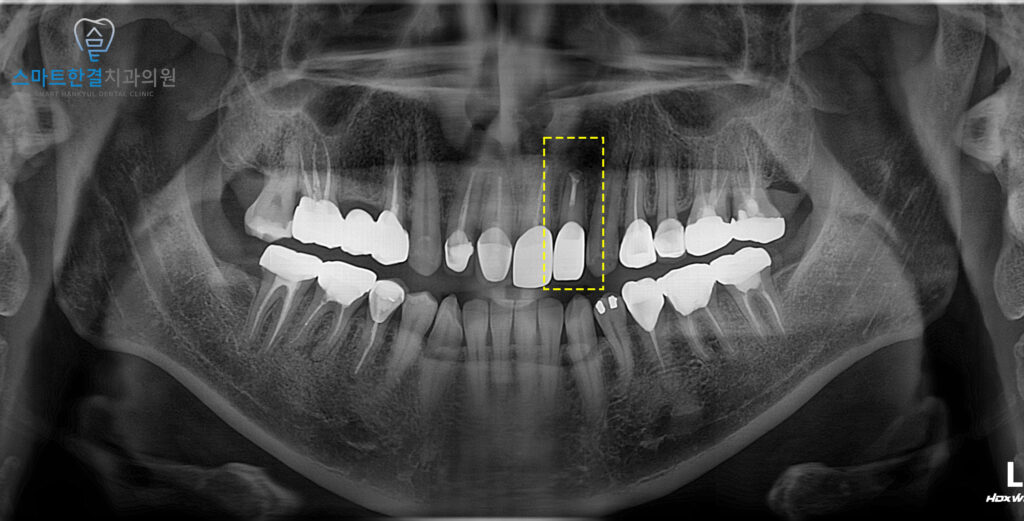

이렇게 재신경치료가 끝난 후

염증이 발생한 뿌리 끝 부분을 절제하여

염증을 완전히 제거하고

치아를 보존할 수 있도록 했어요.

이후 염증이 가라앉고,

치아의 상태가 안정될 때까지

시간을 기다린 후,

치아의 기능과 외관을 회복하기 위해

새로운 보철물을 제작했어요.

재신경치료와 치근단절제술을

병행하여 염증이 제거된 후,

치아의 상태는 안정되었고

최종적으로 치아를 보존하며

건강한 기능을 회복할 수 있는

결과를 얻을 수 있었어요.^^

팔달구치과 스마트한결의

치료 전후 사진이에요.

처음과 다르게 염증이

줄어든게 보이시나요?